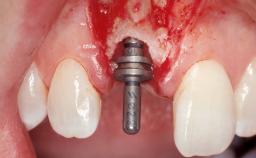

A 39-year-old male patient presented with a chief complaint of discomfort and gingival discoloration around his maxillary left central incisor. He was in good general health and was a non-smoker. His past dental history was significant because of the traumatic fracture of tooth 21 in a sporting accident at age 13. Initial dental treatment included endodontic therapy and a full-coverage restoration. The patient became symptomatic 5 years later, when structural failure of the tooth resulted in the dislodgment of the crown. Endodontic retreatment, apical surgery, and post-and-core restoration were performed.

| Bone Augmentation | Horizontal|Staged |

| Bone Volume | Deficient horizontally, requiring prior grafting |